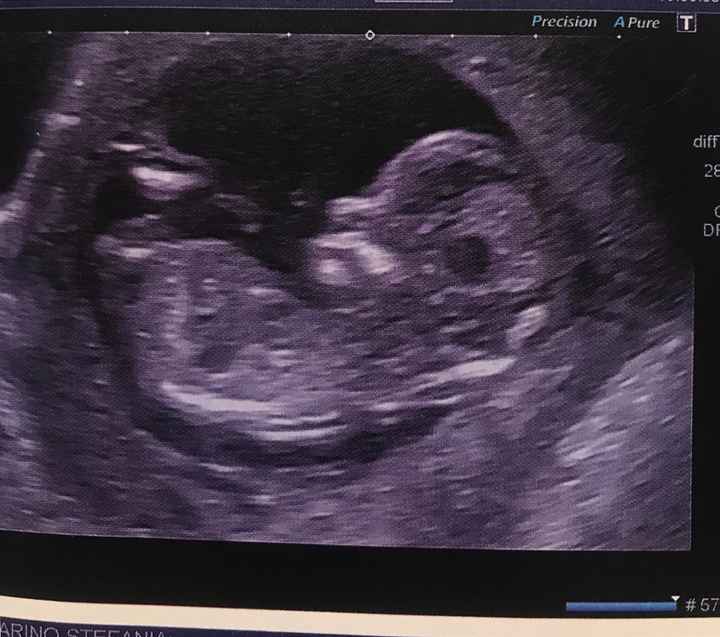

Ciao!! Posso chiedere anche io il

Vostro parere?? Sono due gemelli.. vi metto entrambe le foto della TN. Grazie mille!!Nub theory 9 Nub theory 10

Sono in due sacche differenti? Sembrerebbero un maschio ed una femmina ma non farci affidamento! È un gioco!! Tu hai sensazioni?